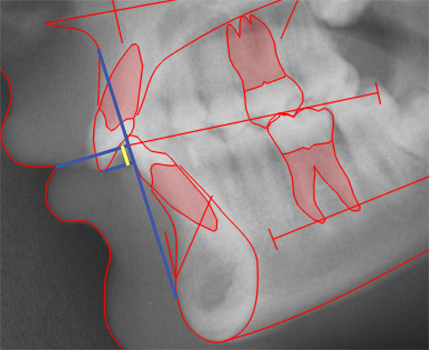

CEPHALOMETRIC MORPHOLOGICAL ANALYSIS

The illustations on this introduction page are discussed in detail in:

Cephalometric Morphological Analysis Parameters

Jens Bjoern-Joergensen, DDS, TIOPS ApS, Roskilde, Denmark

Ib Leth Nielsen, DDS, Division of Orthodontics, University of California, San Francisco

Example of variable values calculation sheet